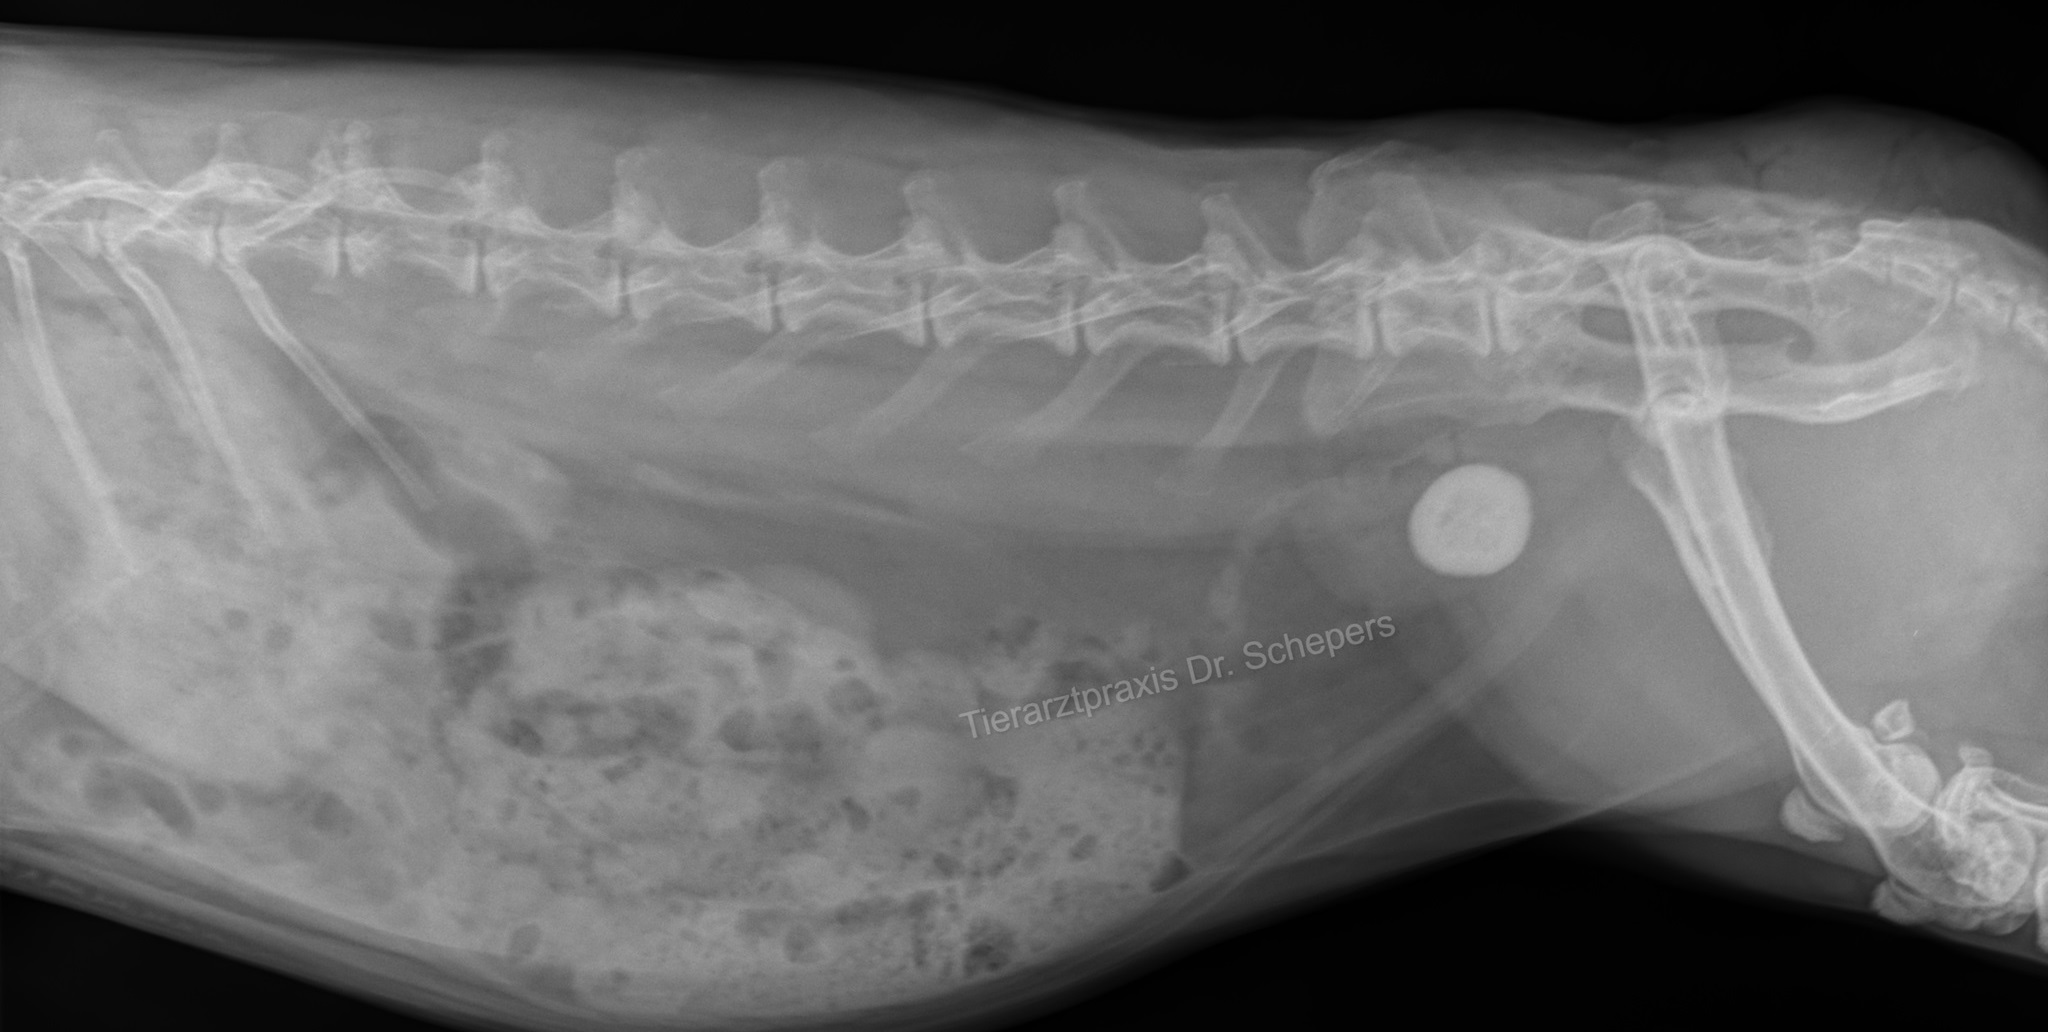

Röntgen: Auf Röntgenbildern sind Kalziumablagerungen als schneeweiße "Wolken" und Steine als solide weiße "Kreise" deutlich erkennbar. Auch Kalziumablagerungen in der Aorta und im Knochengewebe sind deutlich erkennbar. Im Gegensatz zum Ultraschall sind hier außerdem auch Steine sichtbar, die bereits in die Harnröhre gewandert sind. Um die Lokalisation zu bestimmen, sind zwei Aufnahmen aus unterschiedlichen Ebenen notwendig.

Da im Falle einer Blasenkalzinose häufig auch der übrige Harntrakt betroffen ist, sollte unbedingt ein Ganzkörperröntgen angefertigt und beim Ultraschall auch die Nieren mit kontrolliert werden.